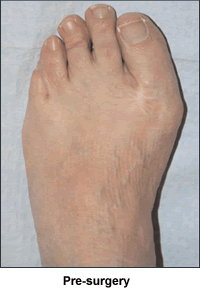

I was born with bunions. When I was 12 years old, my mother took me to a podiatrist for help. He said I was too young, and come back when I'd finished growing. So when I was 23 and had my own health coverage, I went to an orthopedic surgeon by myself. Now I didn't just have 2 little bunions. My toes were all crooked. My big toes went out at sharp 45 degree angles before coming back in. The doctor agreed both feet needed surgery, one just for cosmetic reasons if nothing else. So he sawed off the bunions and lengthened the ligaments between the big and 1st toes on both feet. On my left foot, he also broke the big toe and tried to turn the bone back in at a more appropriate angle. After much pain and recuperation, I decided my feet were "fixed".

Unfortunately, though, if I stood for long periods of time during the day, by the time I would lie in bed at night, it felt as if someone was hitting the soles of my feet with a rubber hose. As I got older, my feet started changing, but not for the better. Both feet still had the big toes going out at 45-degree angles; the bone breaking did not help. My feet were getting wider, the toe area was splayed, but the toes themselves angled into a point at the end of my feet. One toe was starting to cross horizontally over another toe. I was aghast to realize that my toes were definitely turning into my mother's toes.

I felt foolish at the appointment, because my feet weren't particularly hurting, I hadn't had an accident and they were just my "normal" feet. Dr. Leavitt was amazed looking at the x-rays at how deformed my feet really were. He had such compassion and empathy and stressed how the operations would be major ones, but that he could really fix my feet from the metatarsal on. Not many doctors could do this. My first doctor definitely did not. When he broke my toe, he was putting a splint on the top of a tree that was crooked at the base (Dr. Leavitt's analogy). Dr. Leavitt said to take my time and think about it because I would be unable to use each foot for 8-10 weeks. A wave of shock and gratitude swept through me as I realized he was talking about giving me totally normal feet. I wanted to get started and shortly thereafter Dr. Leavitt operated on my first foot. Six months later, he operated on my other foot. I have a cast on as I write these words.